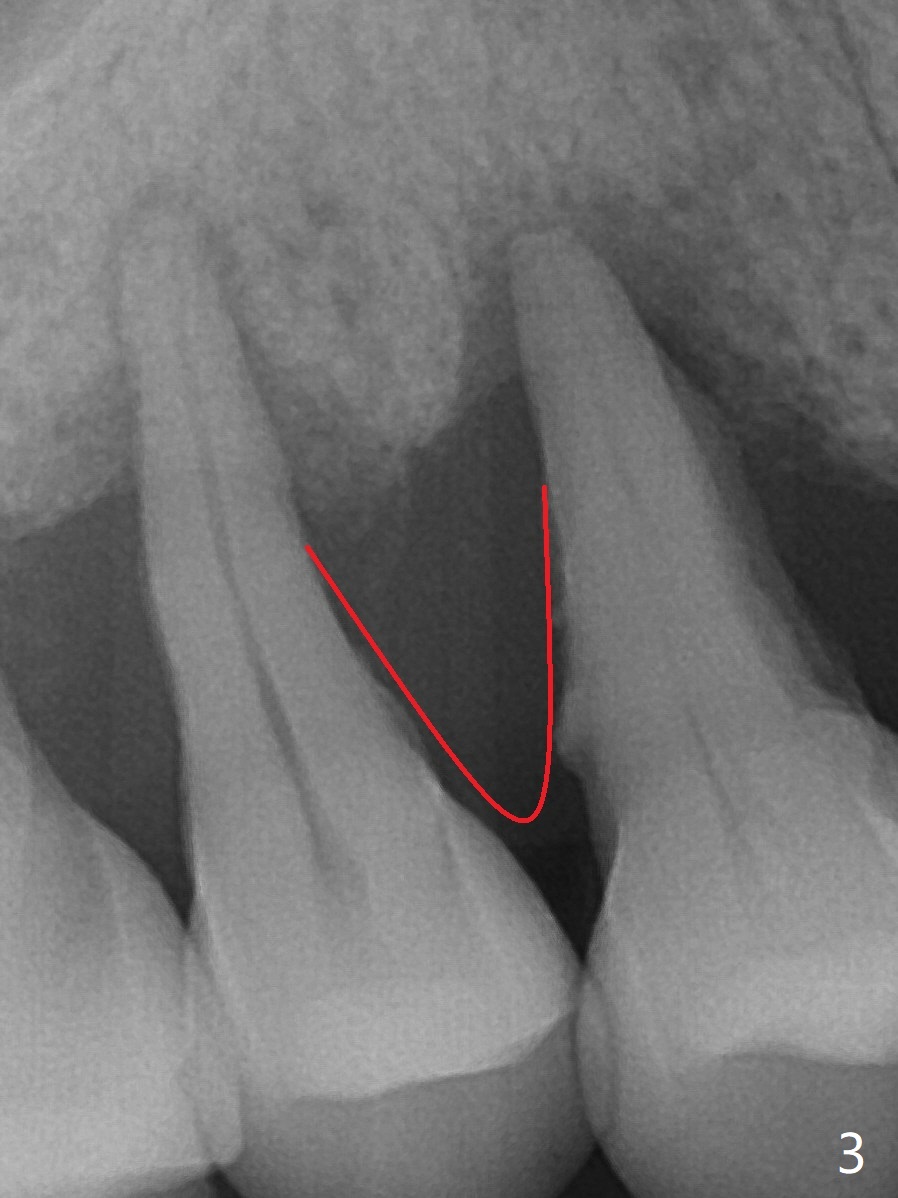

48岁女右上4,5骨质吸收松动五年里逐渐加重(图一,二),而牙龈退缩没那么明显。这两个后牙能同时拔除,种植吗?

图三红线代表龈乳头,当两个邻牙拔除后,没有特殊处理,龈乳头不可避免收缩(图四)。如何预防呢?拔除4时,发现牙槽窝肉芽组织延申到牙槽嵴与乳头之间(图五:黄色)。刮治肉芽组织后,在空缺处,填入粘性骨粉(图六:圆圈),应该能够减少术后龈乳头萎缩。